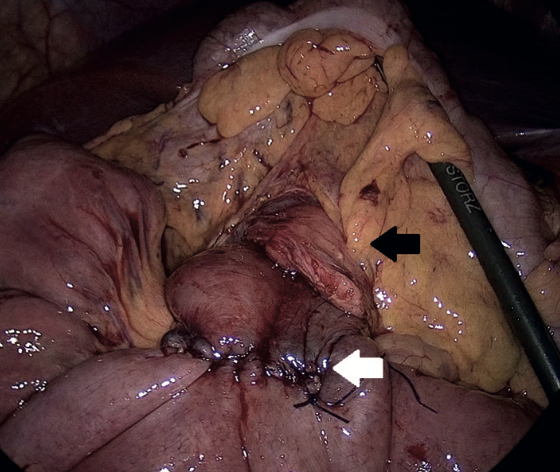

Imágenes y Cirugía

Beatriz Remezal Serrano, Mónica Patricia Rey Riveiro, Pilar Serrano Paz